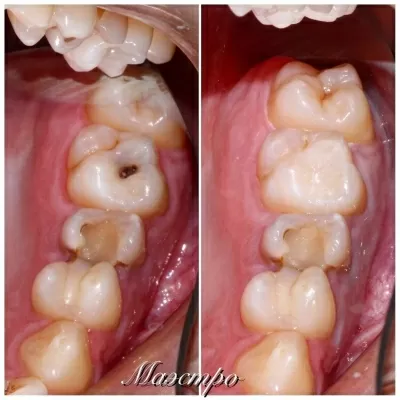

Хочу поблагодарить коллектив стоматологической клиники маэстро!!!Доктора Бардакова Игоря Викторовича и его замечательную команду, за высокий профессионализм чуткость и понимание к своим клиентам!!! Спасибо большое мои дорогие!!! Рекомендую всем кому не безразлична своя улыбка!! Приходите смело в клинику МАЭСТРО не ошибётесь!!!С Уважением Шахова раиса павловна

В стоматологическую клинику МАЭСТРО я пришла по рекомендации.Встретили меня очень тепло.ДОКТОР Игорь Викторович профессионал и умница. Зубы мои стали красивые, а я счастливая.Коллектив у Игоря Викторовича достойный.Как семья.Так приятно.СПАСИБО всему коллективу! Здоровья вам счастья,удачи,мира! Рекомендую всем, кому не все равно как выглядит ваша улыбка и здоровье ваших зубов читать далее